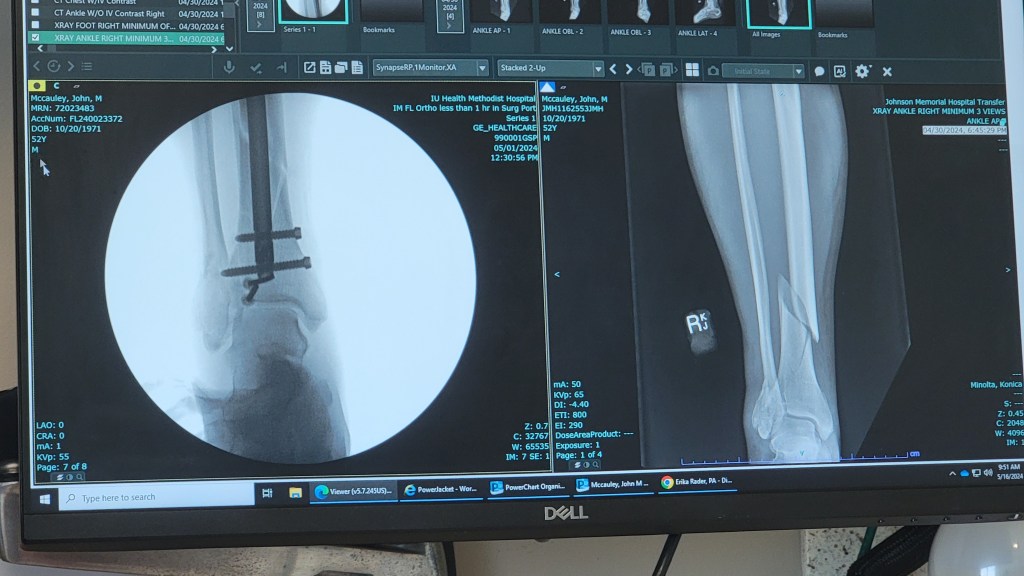

Then came the motorcycle accident. On April 30th, I was going to watch one of Meagan’s last track meets. The weather was really nice and I’d decided to leave a little early and take the motorcycle on some back roads that I’d recently discovered on the way up to Plainfield. I wasn’t 5 minutes from the house, headed south off of IN-44 on Peavine Road, when I went a little too sharply into a curve to the right. The shadows being cast onto the road at that time of day hid some gravel on the road. My back tire hit the gravel, the bike went out from under me, and the bike slammed down onto my right leg. My tibia sustained a spiral fracture, and my fibula was fractured along with some bones in my ankle. Off to the ER at Johnson County Memorial in Franklin and then eventually to IU Health / Methodist Hospital in downtown Indianapolis for surgery. The recovery time includes 4-6 weeks off of the leg and about a 6-12 month full recovery time. The recovery is about 4 weeks in at this point and so far going well, but you can imagine how this effects the renovation progress.